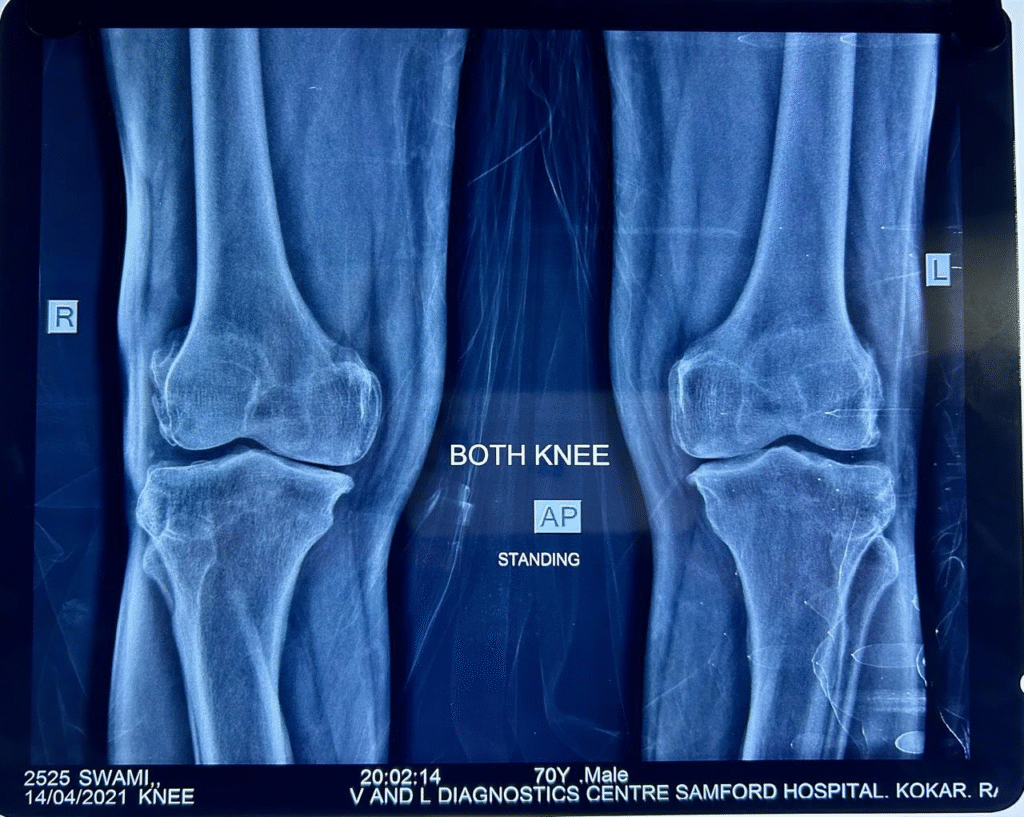

I am happy to say that after using Arthryt Pack for the past 7 years, the diagnosis changed! In 2021, the orthopaedic surgeon said that knee replacement is not needed for the rest of my life. Thanks to Arthryt Pack.

Recent X-ray (dated 14/4/2021) shows no further progression of OA.

April 2021

April 2021